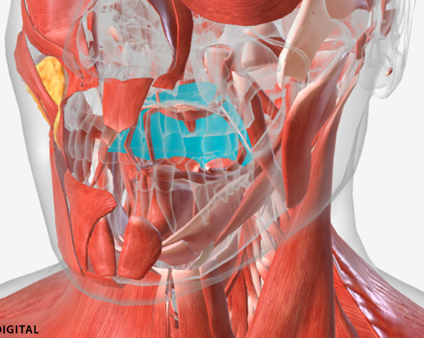

Tensor veli palatini

origin is on the sphenoid bone, coursing down to a tendon wrapping down around the pterygoid hamulus (of the sphenoid), then directed medially to the palatal aponeurosis; function is to dilate the Eustachian tube

Palatine glands

A

Palatine aponeurosis

B

Tensor veli palatini

C

Pterygoid hamulus

D

Levator veli palatini

E